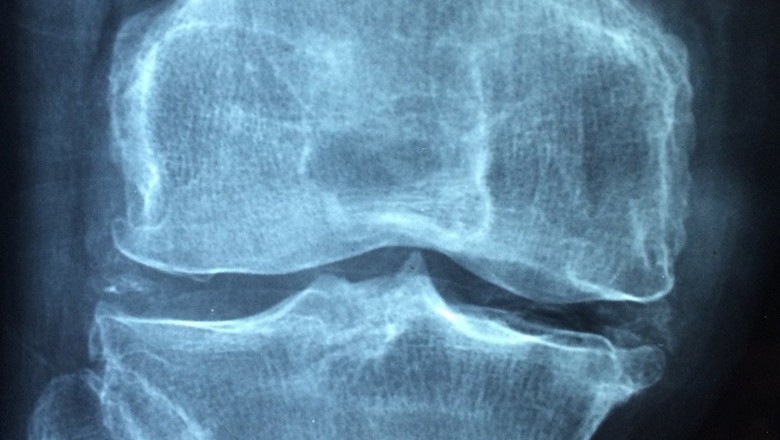

Du Huo Ji Sheng Wan for rheumatic arthritis, rheumatoid arthritis, rheumatic back pain, and sciatica

Du Huo Ji Sheng Wan is a popular herbal medicine in China. It is highly recommended as a cure for rheumatic arthritis, rheumatic back pain, rheumatoid arthritis and sciatica. This herbal formula was developed after long term thorough research and used to enhance the circulation of blood in the body. It also assists in regulating the skeletal system of the body in a healthy way. The herbal therapists of China call Du Huo Ji Sheng Wan a biologically active medicine that is pure and is of the best quality. Its major function is to keep warm and nourishing the flow of Qi in the body. It also reinforces the bones and muscles and regulates the flow of blood in the veins, arteries and tissues.

Du Huo Ji Sheng Wan is also applicable for the stiffness of legs and waist. It is suggested for the patients who are suffering from spasmodic pain in bones and muscles, weakness of lower extremities and knees and for pain in the knees and back. All the ingredients that are used in the manufacturing of Du Huo Ji Sheng Wan are the herbs and roots of very good quality with excellent medicinal value. The major ingredients that are used in the production of Du Huo Ji Sheng Wan include Pubescent Angelica, Codonopsis, Lorunthus, Cortex Eucommia E, and Poria.